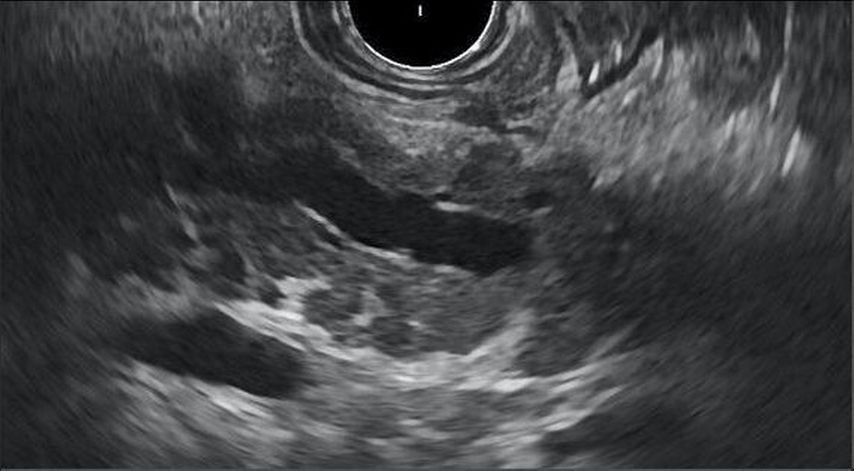

Abb. 1: Endosonografisches Bild einer chronischen Pankreatitis. Eigene Daten zeigen, dass die chronische Bauchspeicheldrüsenentzündung bei HIV-Infizierten häufiger als in der HIV-negativen Population vorliegt. Sie findet sich bei 21% der Untersuchten, während die Prävalenz bei Nichtinfizierten nach Literaturangaben bei max. 1‰ liegt (Göbbert A. 2023)10. Dieser klinisch relevante Befund untermauert die These, dass das Krankheitsspektrum oft weit über den Status der HIV-Positivität hinausgeht. Die Komorbiditäten, die zusätzlich zur Grunderkrankung vorliegen, erfordern Zuwendung, diagnostische Bemühungen und konsequentes Management. Dies kann nur gelingen, wenn die Versorgung aktiv koordiniert bzw. gelenkt wird. Hier fungieren Infektiolog:innen als zentrales Stellglied